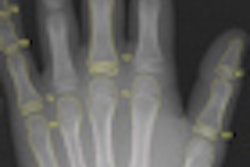

Vatech delivered two 17 x 17-inch fixed panels and a portable 10 x 12-inch flat-panel detector for extremity work. Nassau students, who have been using both computed radiography (CR) and analog x-ray machines for training, now have DR technology available as well, according to Vatech.